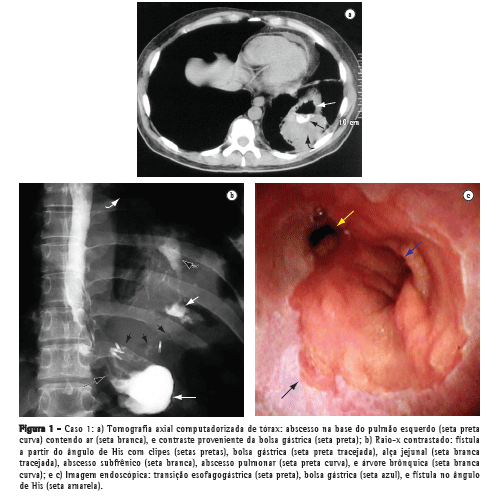

Um paciente do sexo masculino com 44 anos de idade submeteu-se à cirurgia de Fobi-Capella por videolaparoscopia para controle da obesidade mórbida, sendo reoperado após 48 h para tratamento de obstrução intestinal. Dois meses depois, foram realizadas duas sessões de dilatação endoscópica com balão para correção de estenose da anastomose gastrojejunal. Em seguida, o paciente apresentou quadro de vômica, tosse produtiva, febre e dor à inspiração profunda na região tóraco-abdominal esquerda, sendo diagnosticada uma imagem nodular de 7 cm de diâmetro, em base pulmonar esquerda, por meio de tomografia axial computadorizada de tórax (Figura 1a). O paciente apresentou melhora clínica após antibioticoterapia, fisioterapia respiratória e acompanhamento no serviço de pneumologia. Porém, houve duas recidivas num intervalo de três meses, quando então foi diagnosticada uma fístula gastrobrônquica por meio de imagem radiológica (Figura 1b) e endoscópica (Figura 1c) que evidenciou um orifício com 10 mm de diâmetro no ângulo de His, através do qual foi possível a passagem do endoscópio até uma pequena cavidade subfrênica onde se visualizava um orifício interno do trajeto fistuloso para a árvore brônquica. Não houve sucesso na tentativa de correção via laparotomia, sendo realizada apenas uma gastrostomia no estômago excluso para nutrição. Assim, usando bisturi elétrico, realizou-se a secção endoscópica da estenose gástrica e do septo situado entre a fístula e a bolsa gástrica associada à dilatação com balão de 20 e 30 mm (Boston Microvasive, Boston, MA, EUA) e aplicação de clipes na fístula (Olympus Corp., Tokyo, Japão). Após seis meses, observou-se aumento do diâmetro da bolsa gástrica, desaparecimento do referido septo e fechamento definitivo da fístula com resolução do abscesso pulmonar.